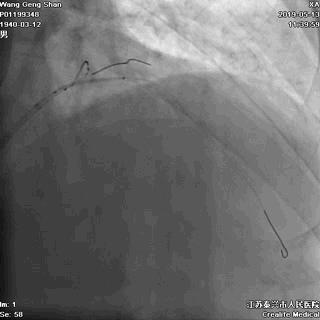

06 LM-LAD支架后扩张

交换回旋支导丝,非顺应性球囊顺序高压扩张

07 LM支架近段优化(POT)

左主干近段用大一号非顺应性球囊行高压扩张

IVUS评估,支架贴壁良好。